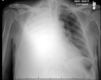

• 91번 환자인 영국인 폐 이식 수술 준비